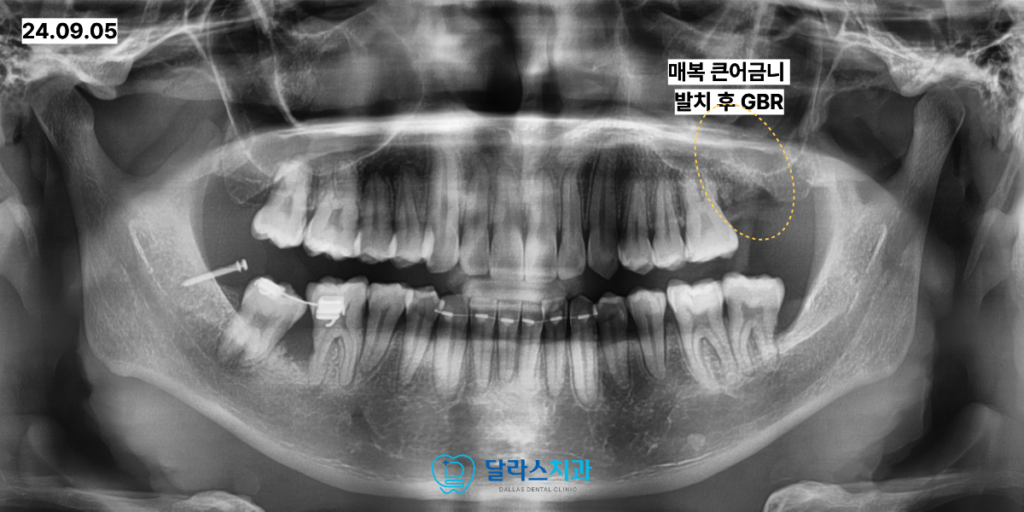

이에 따라 무리한 견인을 시도하기보다는 해당 치아를 발치한 후

부족한 뼈를 채워주는 골이식 술식을 병행하였습니다.

상악동 거상술을 함께 시행하여 임플란트가 식립될 충분한 공간을 확보하였고

최종적으로 임플란트를 식립하여 저작 기능을 회복해 드렸습니다.

인비절라인 교정을 통해 전체 치열을 가지런하게 정리한 뒤

임플란트 부위에 보철이 완성되었으며, 어금니가 바로세워졌습니다.